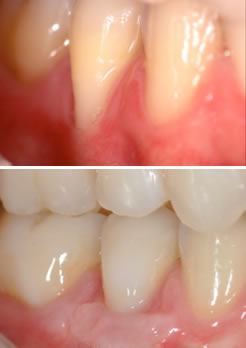

Antes e depois do tratamento